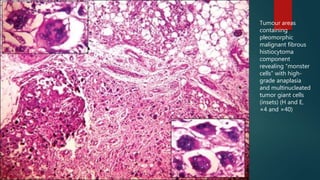

Tumour areas

containing

pleomorphic

malignant fibrous

histiocytoma

component

revealing “monster

cells” with high-

grade anaplasia

and multinucleated

tumor giant cells

(insets) (H and E,

×4 and ×40)

Tumour areas containing pleomorphic malignant fibrous histiocytoma component revealing“monster cells” with high- grade anaplasia and multinucleated tumor giant cells (insets) (H and E, ×4 and ×40)